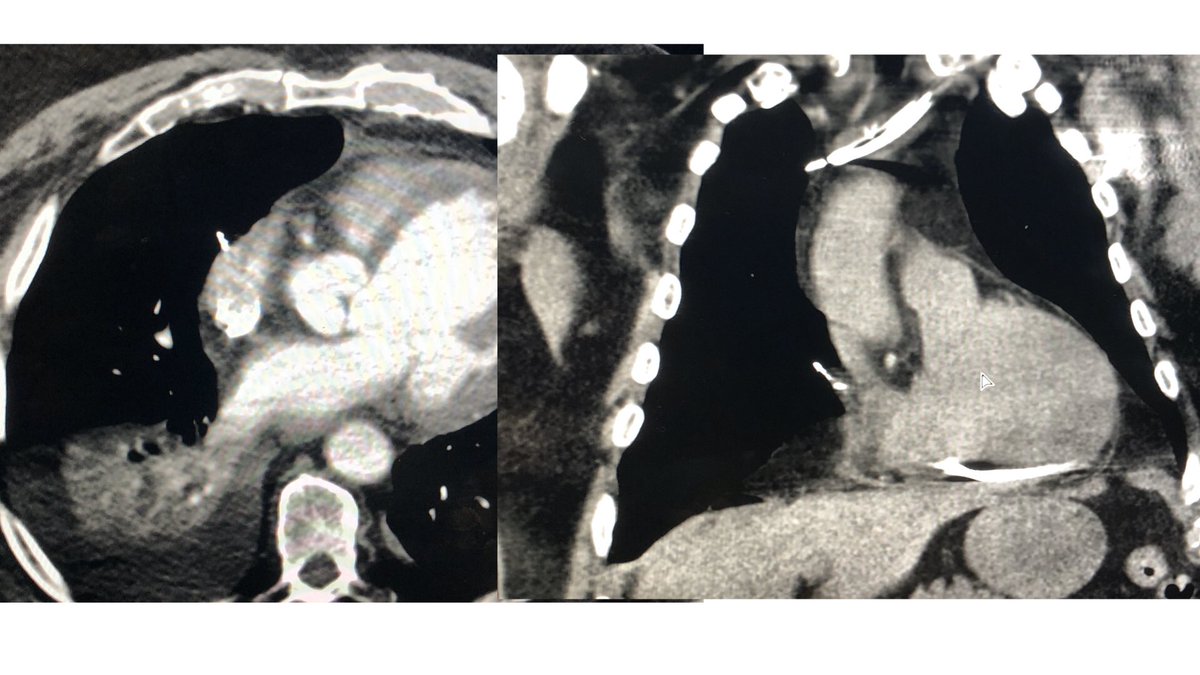

1202-A - Cardiac Devices: Underrecognized Source of Hospital-associated Infections cdmcd.co/Z4zWjX

@HRS2022

Only 18% of patients with device infections are getting prompt lead extraction, What do we need to do to close the gap between guidelines and care?

Prompt lead extraction saves lives! @laserlead @JonPicciniSr #CIEDinfection